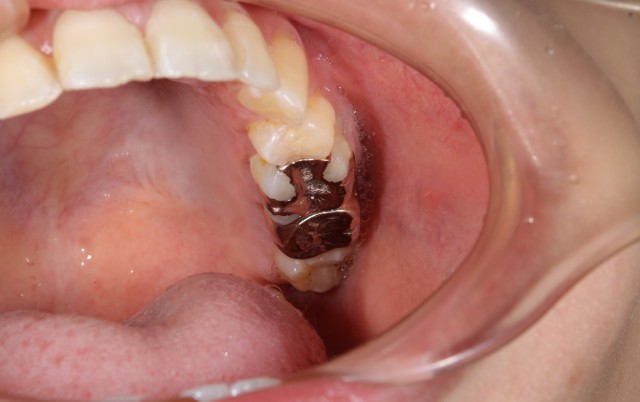

施術前

虫歯の治療でもともと金属にアレルギーがあると判明している方には治療法を考えますが、場所や状態によって金属製の詰め物をして治療することがあります。しかし、もともとアレルギーがなくてもアレルギーが出てくる場合もあります。今回の症例も過去のむし歯の治療によって金属アレルギーによる症状が出てきたので口腔内から金属をなくすメタルフリーによりアレルギー対策を行うという症例をご紹介いたします。